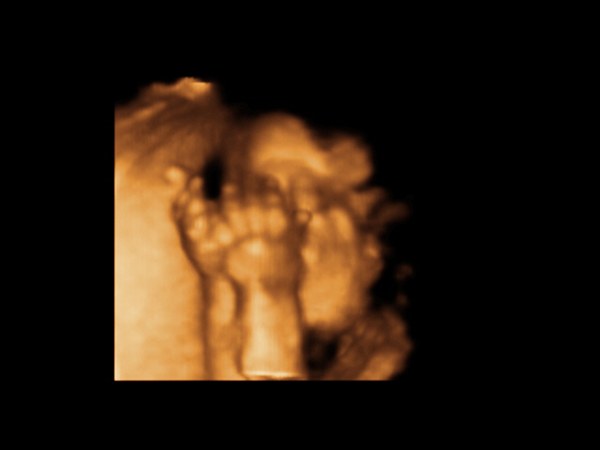

Katica, szuper lehetett ez a vizsgálat, de a legnagyszerűbb, hogy mindent rendben találtak.

Tegnap 3/4 3-tól majdnem 5-ig vártam a dokira, hogy megnézzük Botondot, és, hogy nem okozott-e valami bajt a hételeji tányérbecsapódás a hasamba. A lényeg: nem látszott semmi baj, Botondka is szépen növöget, és képzeljétek a "rohamos súlygyarapodásra" -mert így írta be a kiskönyvembe a védőnő, azt mondta a doki, hogy ne foglalkozzak vele, és viccesen hozzáfűzte: jó, hogy nem szereltetünk be egy futópadot ide a vizsgálóba, hogy aztán még büntessük is a kismamákat, amiért hízni mertek.